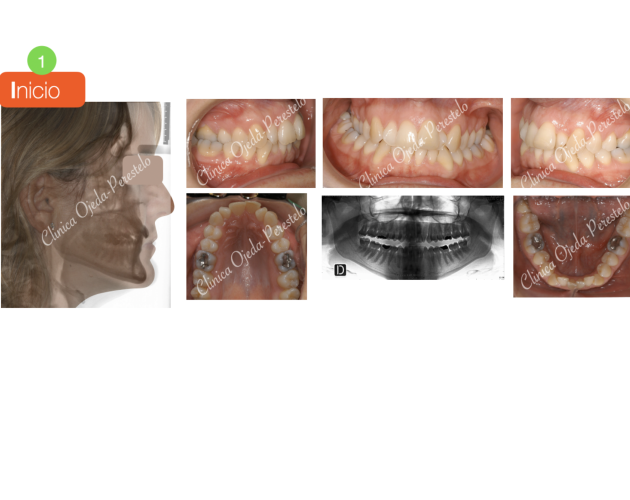

Mordida Abierta de molar a molar Casos de Éxito - Adultos